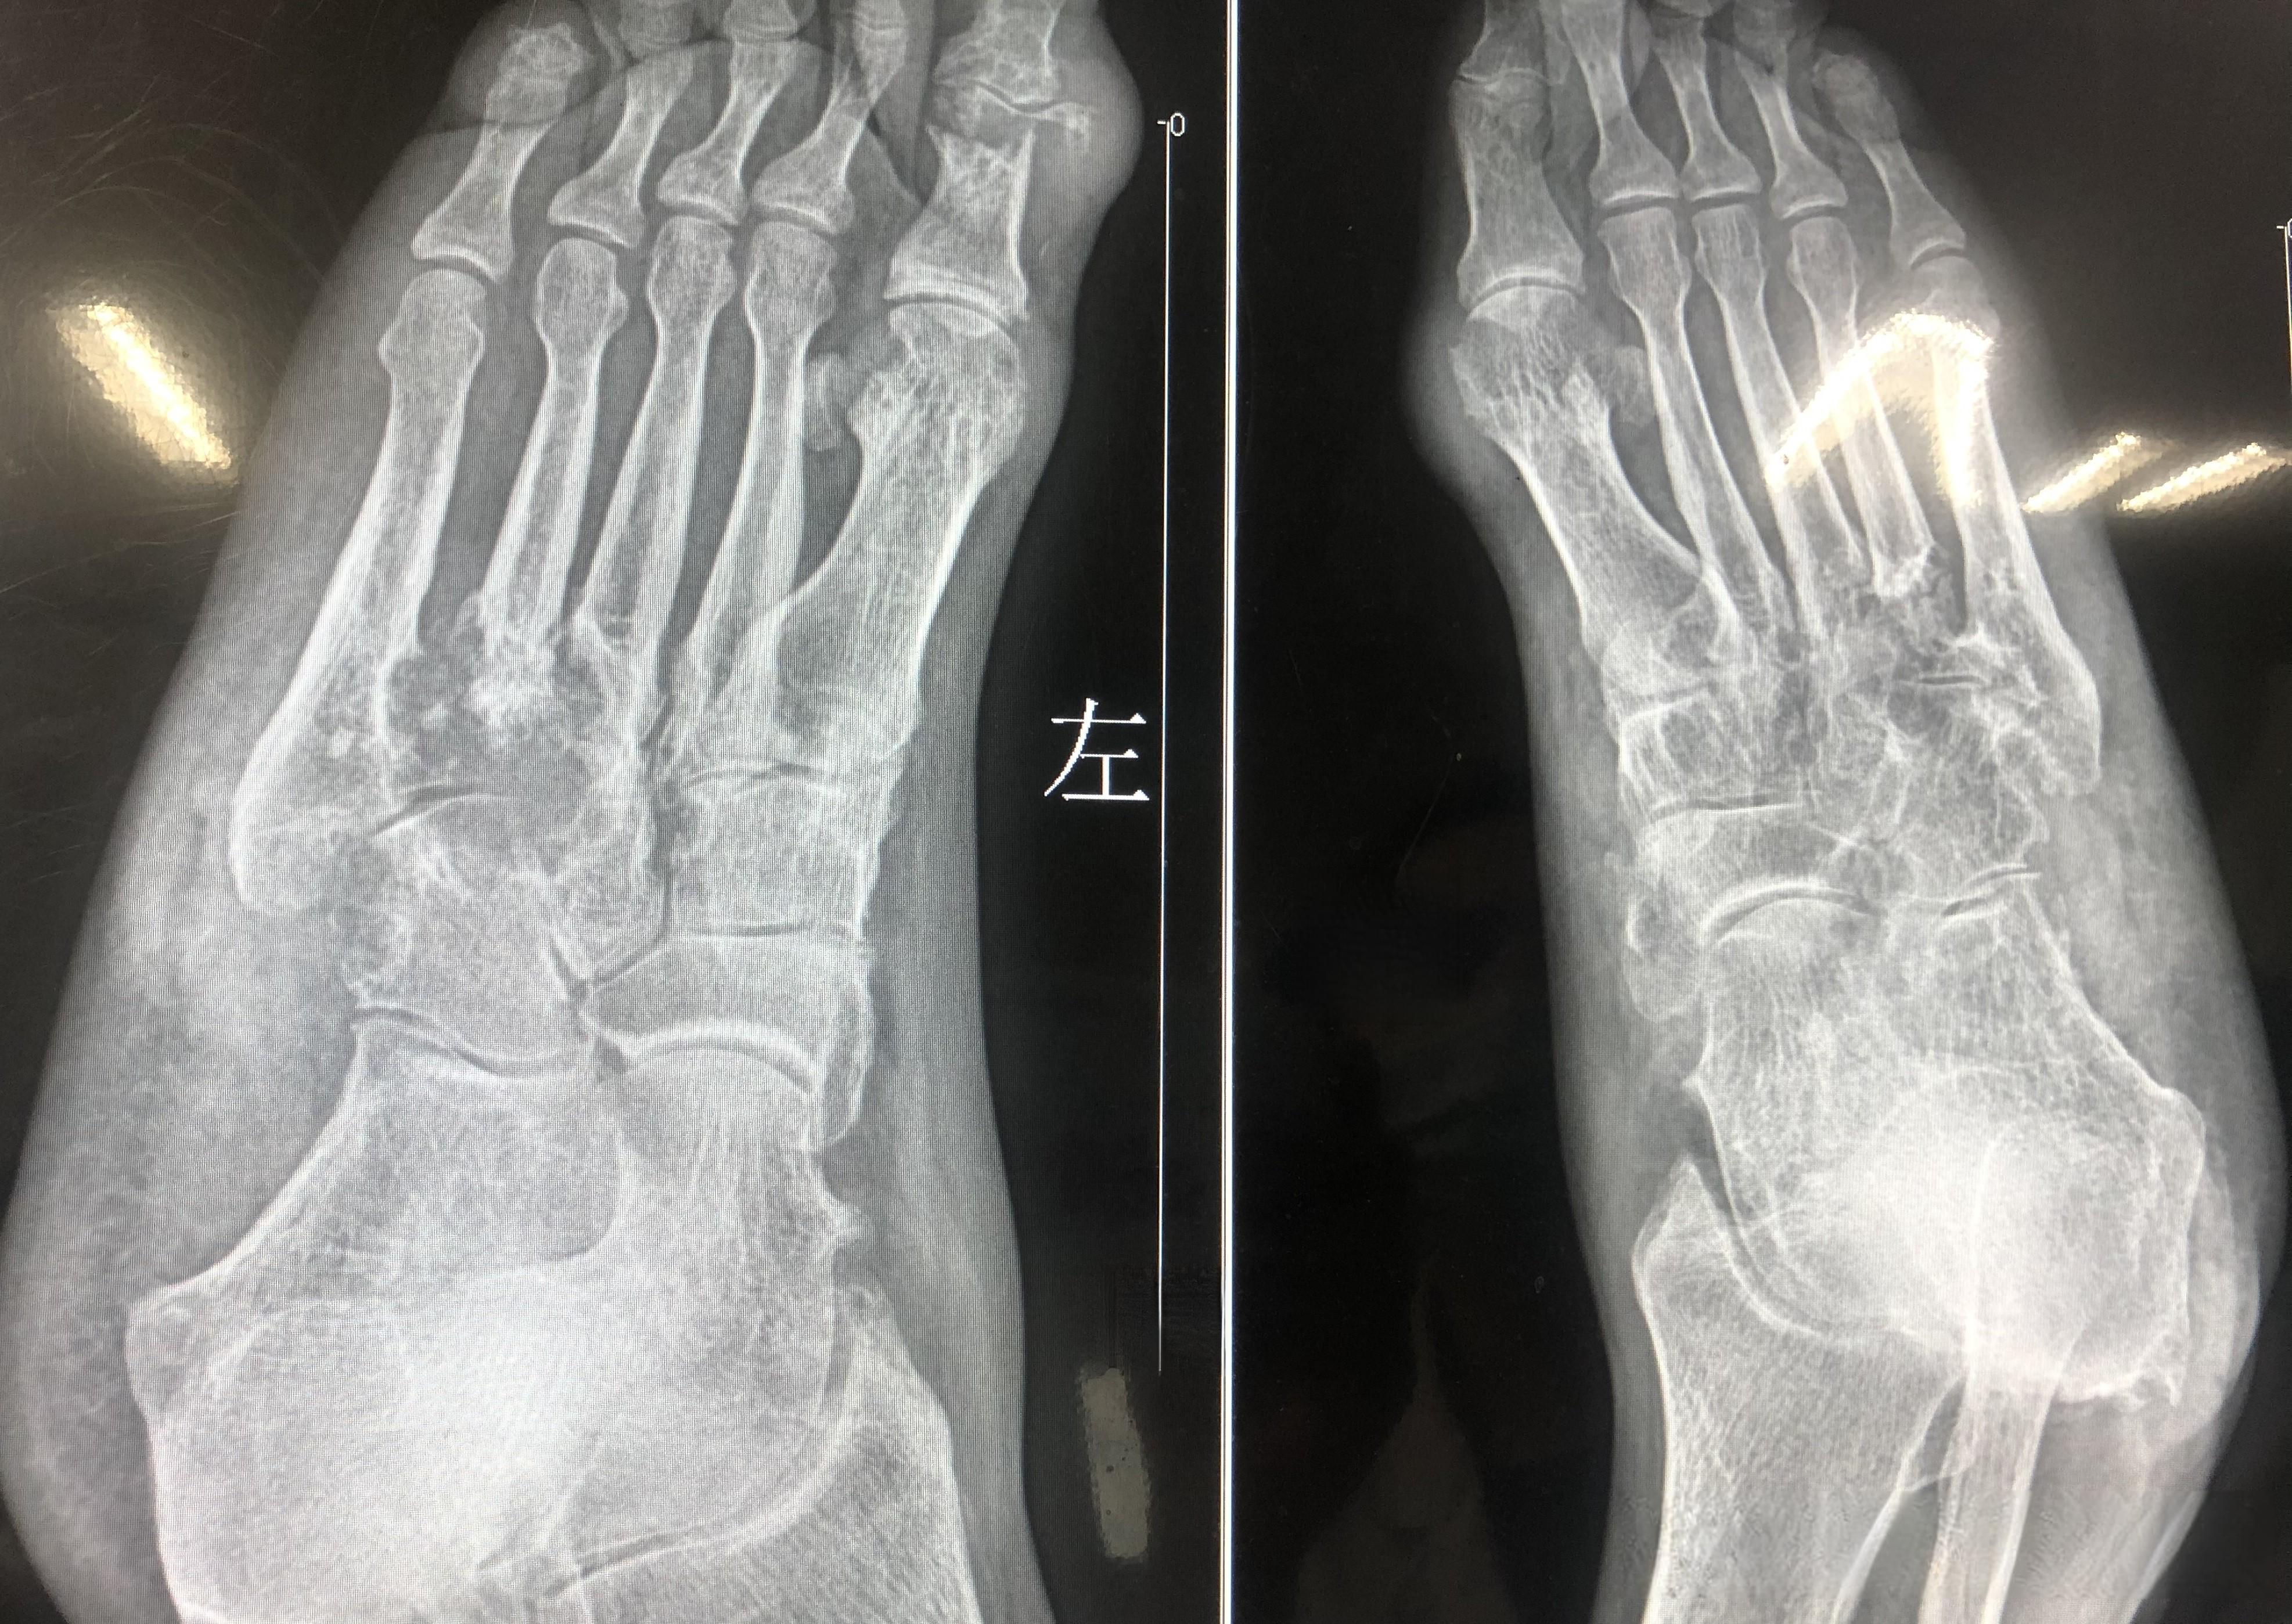

五年痛风三年长石头,他像挤青春痘一样挤痛风石,这样做靠谱吗?

一位痛风患者因为无法忍受痛风石带来的不适,竟然像挤青春痘一样尝试挤压痛风石。这种做法不仅无法解决问题,还可能带来更大的风险。

痛风石,又称痛风结节,是痛风患者体内尿酸盐结晶在皮下聚集形成的结晶。 这些结晶通常出现在关节软骨、滑囊、耳轮、腱鞘、关节周围组织、皮下组织和肾脏间质等处。痛风石的形成与高尿酸血症密切相关,当血液中的尿酸水平长期高于正常范围时,就容易形成这些结晶。